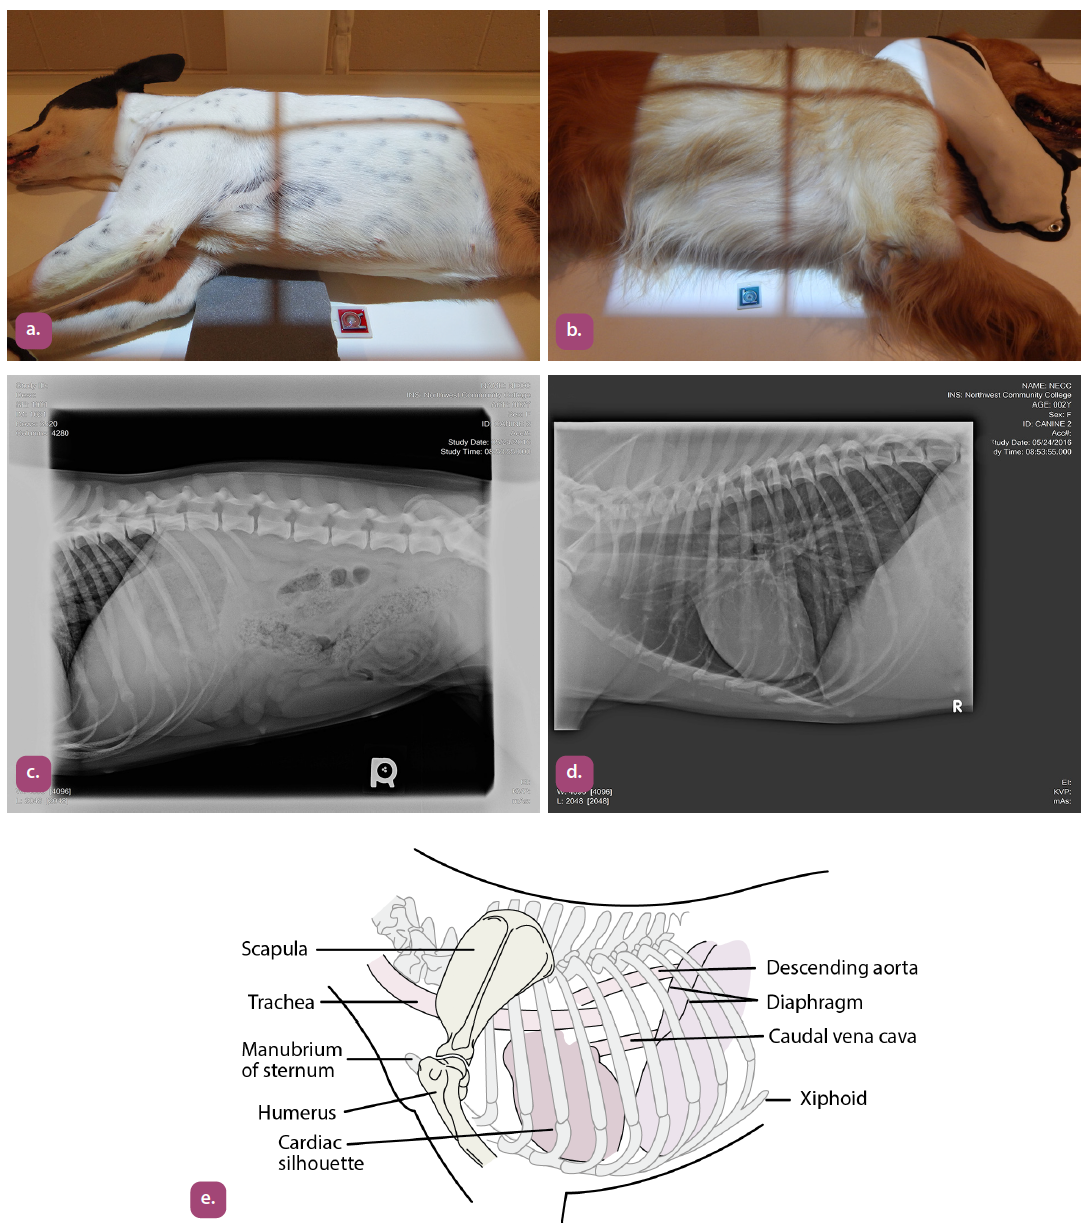

lateral projection of the thorax